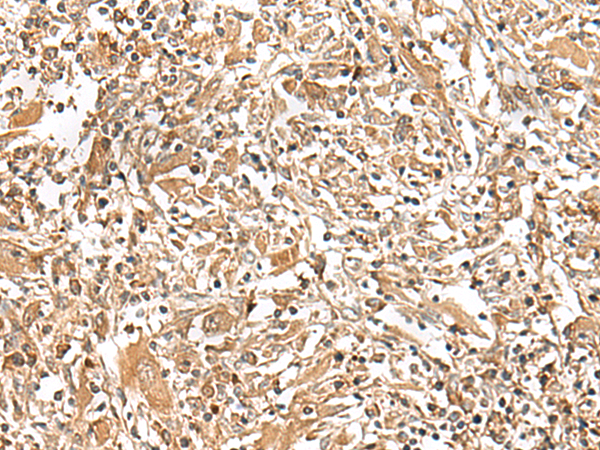

IHC positive control: |

Human liver cancer and Human esophagus cancer |

IHC Recommend dilution: |

30-150 |